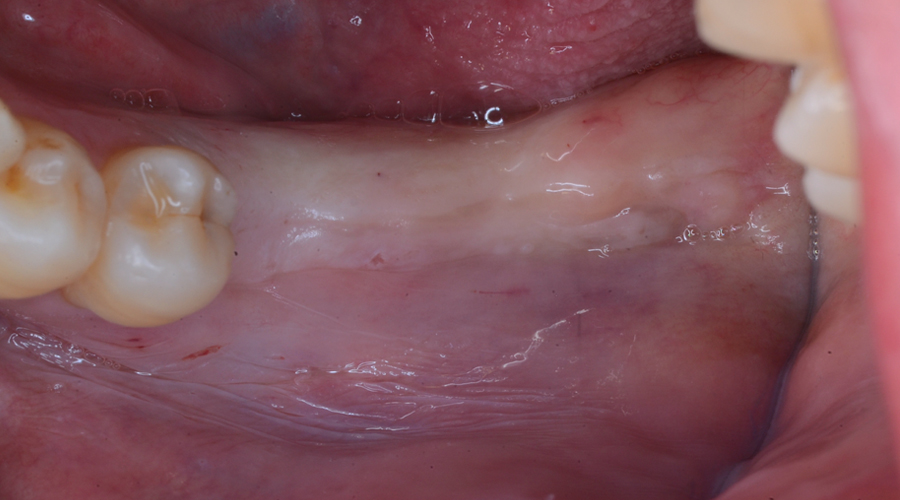

- 治療内容

- 欠損部位に対して、人工歯根を埋入し上部構造として補綴物をかぶせる治療です。

- 治療に伴うリスク

- 治療後の口腔管理が不適切な場合、埋入したインプラント周囲に感染・炎症を起こし、脱落する可能性がございます。